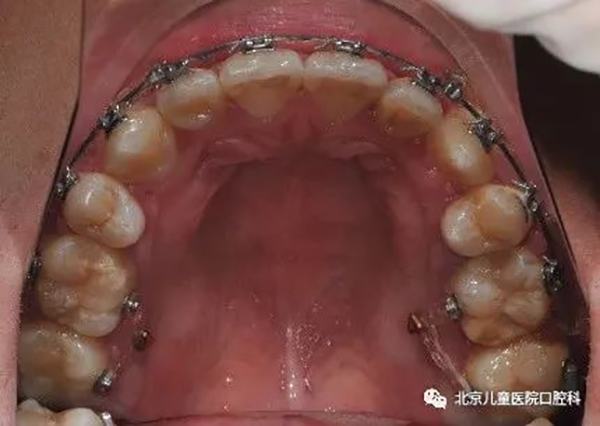

4、前移磨牙,关闭间隙。

治疗前

治疗中

治疗后